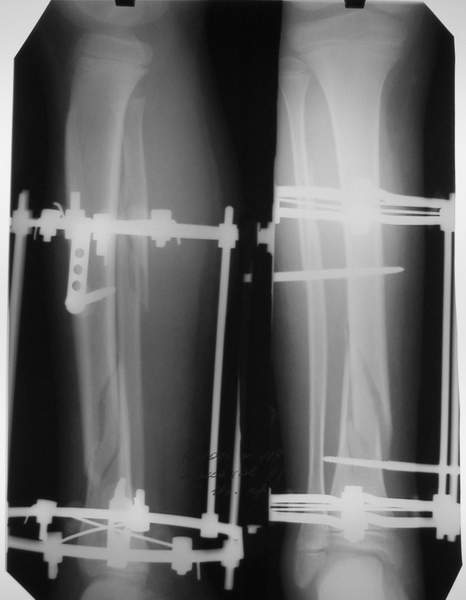

Под рукой прилагаемый пример. Как видите, "стриптиз-аппарат" (шутка проф. З.К.Башурова): 3 кольца-2 кольца-2 полукольца. В случае, который представил Евгений, характер повреждения позволил бы сразу использовать аппарат на основе 2 колец; в крайнем случае прокс. опора м.б. демонтирована сразу после репозиции.

МТ мы используем, конечно, не только на голени. В прилагаемом примере у парня при поступлении была наружная ротация 40 гр. и "полумертвый" коленный сустав. Можно был бы, конечно, до конца использовать полную компоновку. Но для того он и есть метод выбора.

3a

3b

3c

В аттачте № 3 - один из примеров полукольцевого аппарат...

Это уже я баловался.

Итог? Работы больше (по времени и

интраоп "подгонке"), срастается также, а особого преимущества по сравнению с

"чиста" кольцевым (вес, удобство ношения и пр.) - я, по крайней мере,

не нашел.

Теперь не балуюсь.